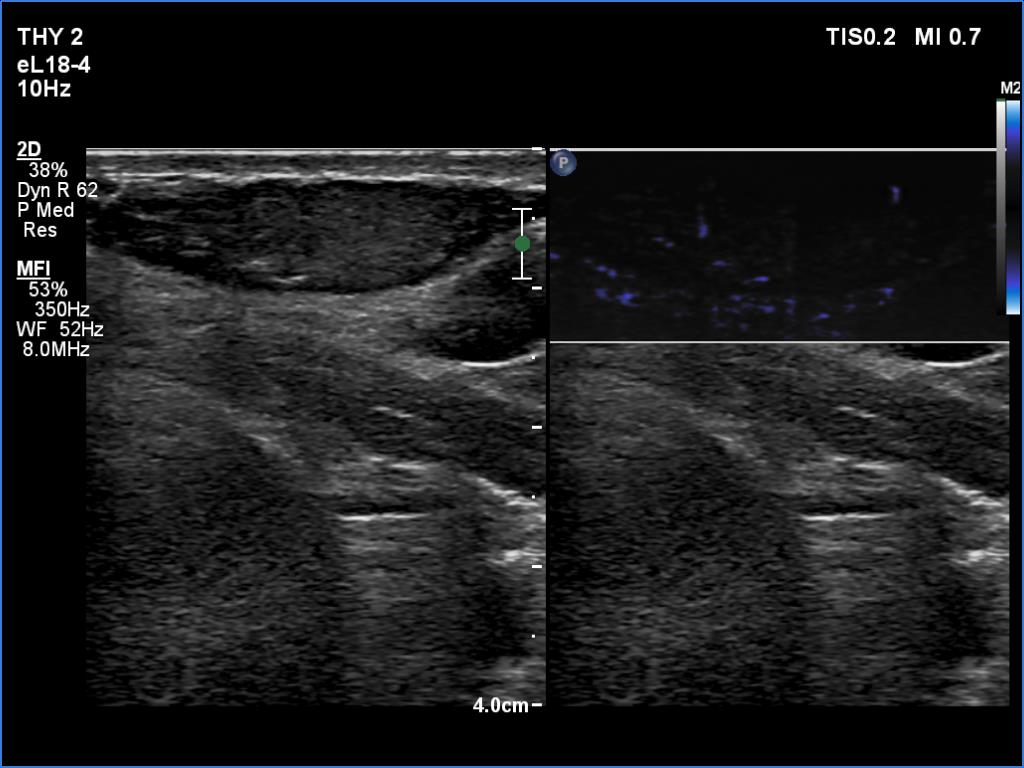

Ultrasonography. The thyroid was echonormal and had several small cystic lesions without any clinical or oncological importance. According to the palpable mass, a moderately hypoechoic lesion was detected several centimeters under the thyroid in the middle of the neck. The lesion was within the muscle tissue. It was homogeneous and presented no vascularity.